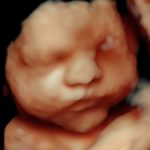

4D/5D/HD Ultrasound Gallery

Gallery